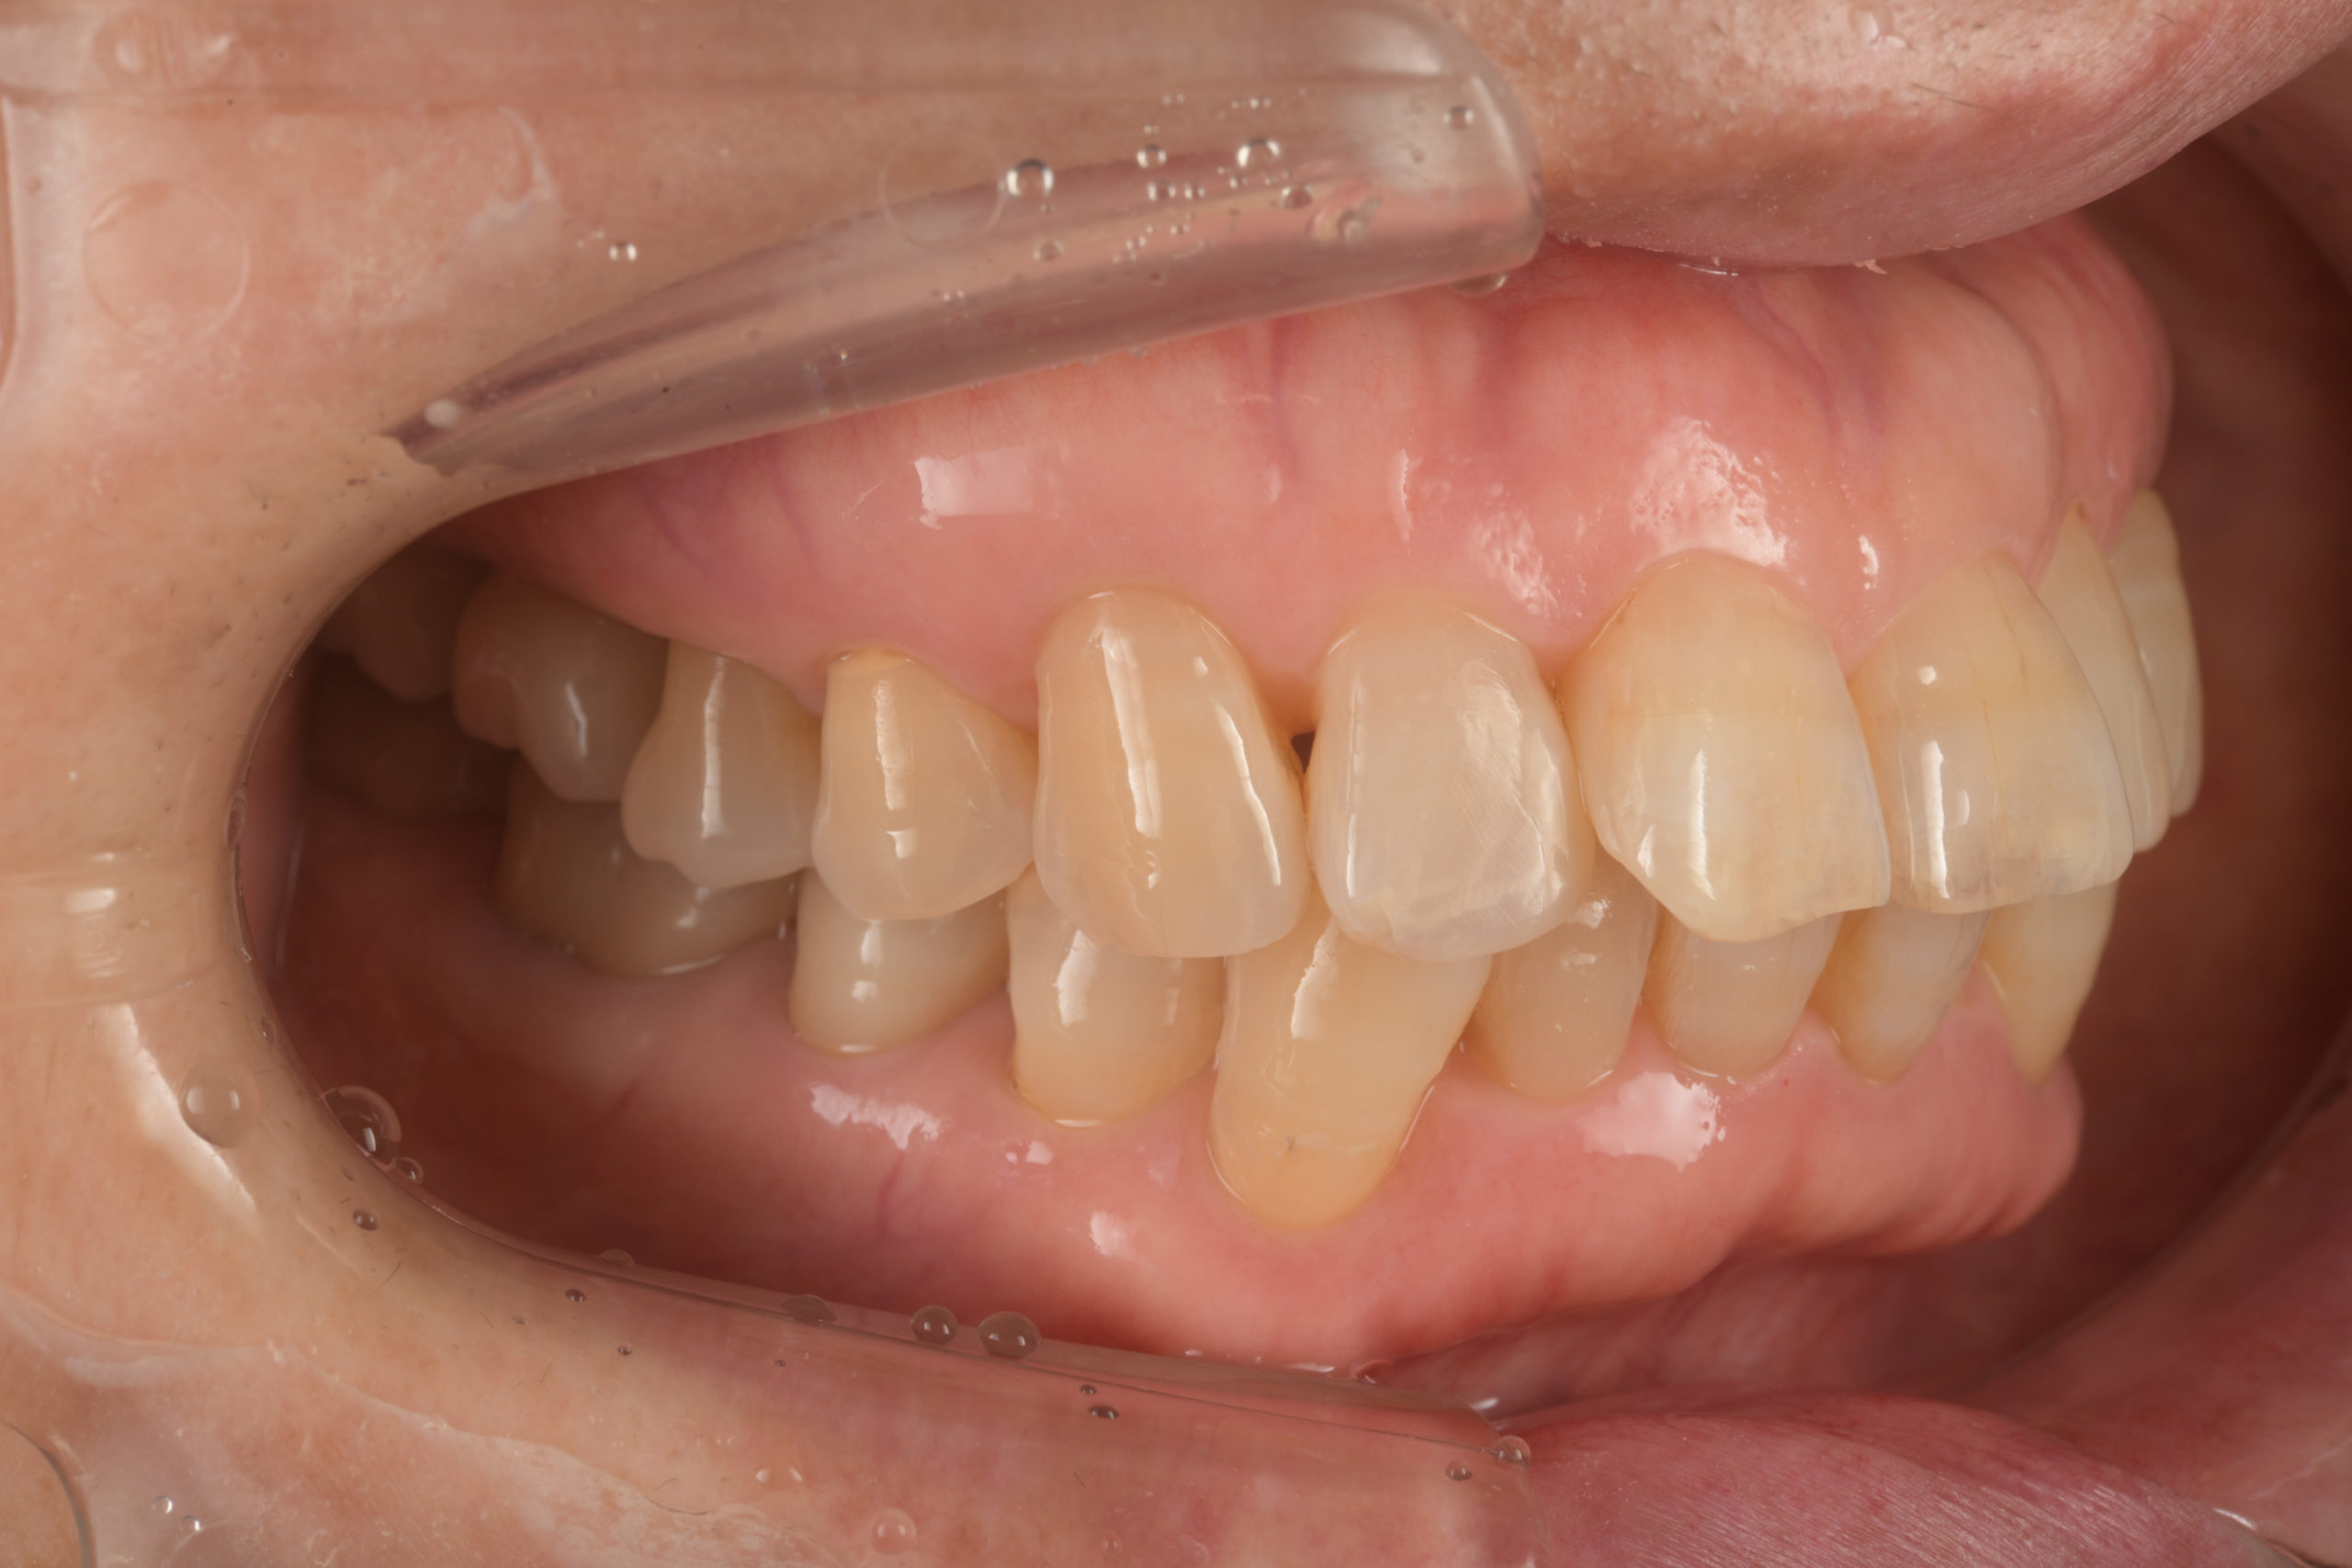

左下臼歯部インプラント治療前

左下臼歯部インプラント上部構造装着前

左下臼歯部インプラント治療完了